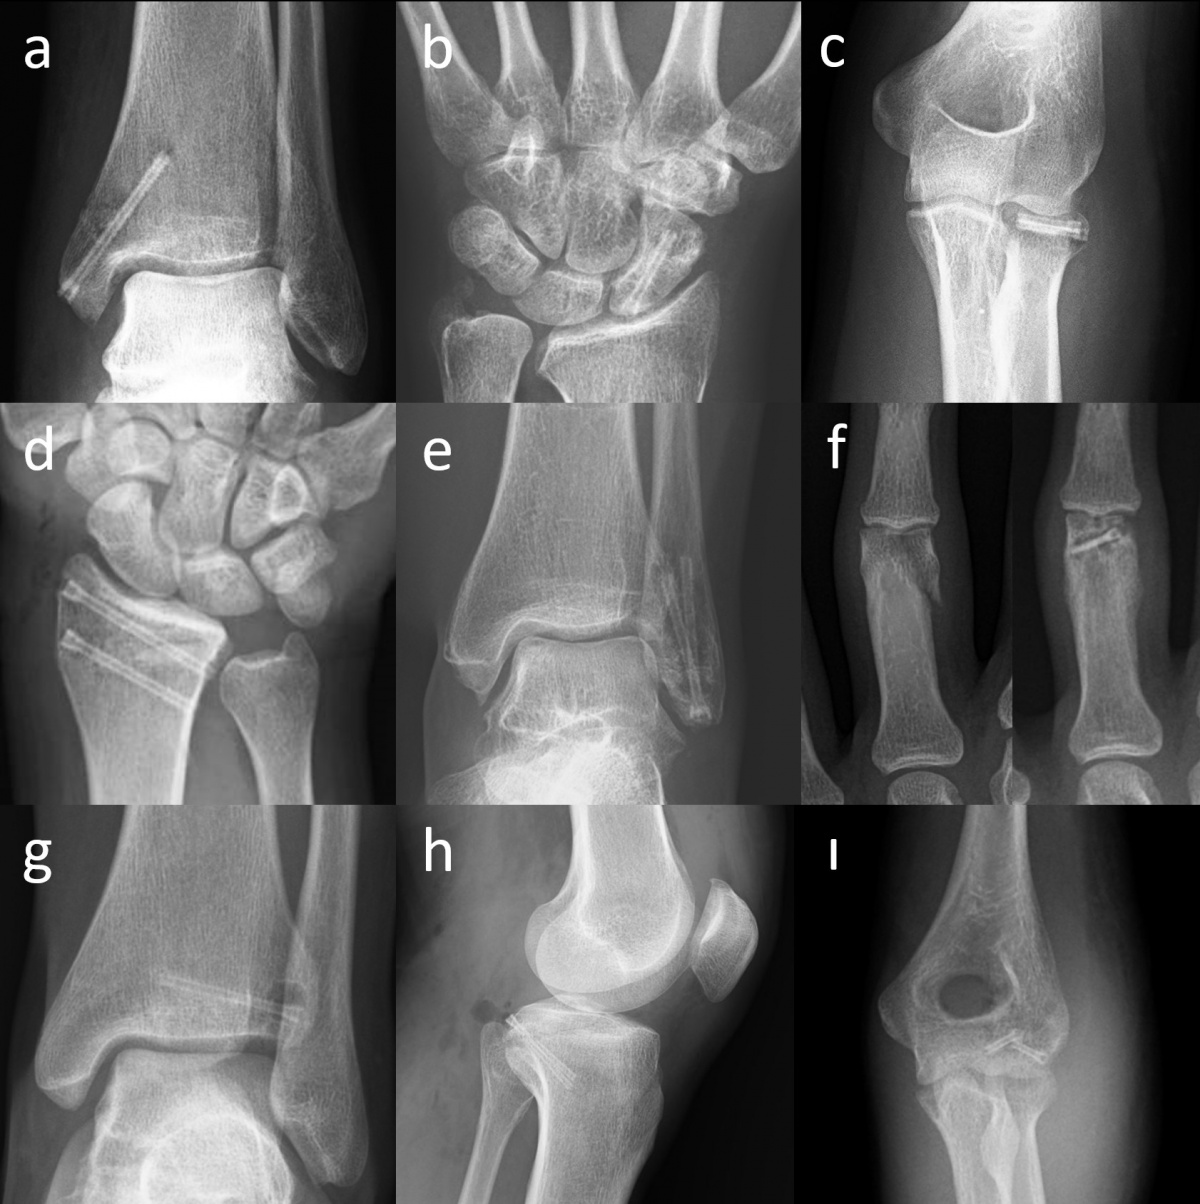

(schwarzer Pfeil) in der präoperativen lateralen Röntgenaufnahme des

Ellenbogens. (b) Röntgenaufnahme des Ellenbogens mit Gasansammlung

im Weichgewebe (weiße Pfeile) am ersten postoperativen Tag. (c)

Röntgenaufnahme des Ellenbogens 25 Tage nach der Operation, die

Gasmenge hat sich verringert (weißer Pfeil). (d) Bei der radiographischen

Nachbeobachtung nach 2 Monaten ist kein Gas im Weichgewebe

mehr sichtbar.

In frühen postoperativen Röntgenaufnahmen lässt sich auch Gas im Weichgewebe beobachten, das sich in den Gewebeschichten verteilt. Klinisch produziert dieses Gas aber keine wahrnehmbare Krepitation unter der Haut oder ähnliche Symptome. Die Gasschatten im Weichgewebe bilden sich gewöhnlich rasch zurück (Abbildung 3). In frühen postoperativen Röntgenaufnahmen stellt Gas im Weichgewebe oft ein alarmierendes Signal dar, da es – bei herkömmlichen Metallimplantaten – mit gasbildenden anaeroben Infektionen in Verbindung gebracht wird. Die Bildung von Gas während der Degradation von Mg-Implantaten hat einen vollkommen anderen Hintergrund – es handelt sich weder um eine Lockerung des Implantates noch gar um eine Infektion. Während des Abbauprozesses via Korrosion nimmt die Gasmenge zu und breitet sich im trabekulären Knochenanteil aus. Schließlich wird es jedoch vollständig resorbiert und die Mg-Schrauben zeichnen sich zunehmend prominenter ab (Abbildung 4). Tierstudien haben gezeigt, dass die Schraube schließlich durch kortikales Knochengewebe ersetzt wird (7).